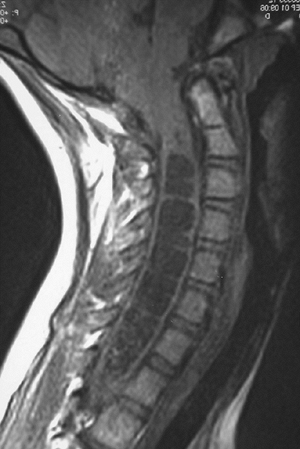

fourth ventricle with the persistent central canal of the cord (Fig. 16.2).

The dilatation of the spinal cord with CSF may be marked by increasing

scoliosis, paralysis of the lower extremities, increased spasticity,

and back pain. Cervical syrinx will also present with spasticity and

weakness of the hands and upper extremities in older teens.

![]() |

|

Figure 16.2

Representative MRI scan of affected individual with Arnold-Chiari malformation and associated hydromyelia (syrinx) of the cervical spine. |